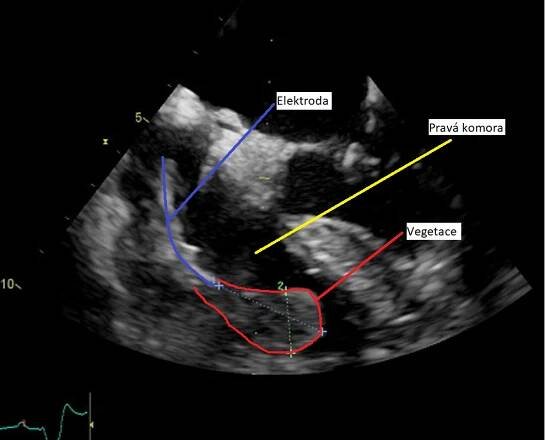

Endokarditida - vegetace na aortální chlopni na TEE

Infekční endokarditida je infekční zánět srdeční nitroblány. Onemocnění přibývá u jedinců bez srdečního onemocnění a s nezměněnými chlopněmi, obvykle po lékařských nitrožilních výkonech, u narkomanů, a dále u pacientů s umělými chlopněmi.